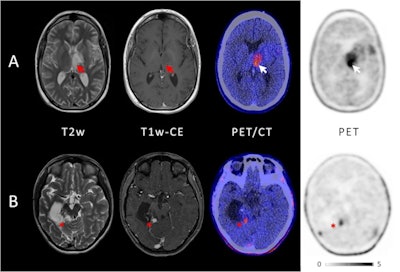

Investigators at the University of Augsburg studied the impact of PET imaging with an amino acid radiotracer (F-18 FET) in pediatric patients with newly diagnosed and previously treated central nervous system (CNS) tumors. In cases where cranial MRI exams failed to provide enough detail, FET-PET scans guided treatment in more than half of the patients, they found.

Fourteen out of the 21 patients showed positive uptake of the FET radiotracer by tumors: three out of five with newly diagnosed brain tumors and 11 out of 16 with previously treated lesions. In these patients, FET-PET had an impact on further treatment decisions, the researchers found.

Specifically, invasive surgery or biopsy was avoided in four patients, and PET was crucial to biopsy or surgery guidance in another four patients. In three patients, FET-PET directly changed further therapy: One patient received chemotherapy instead of radiotherapy, chemotherapy was changed to another regimen in another patient, and one patient received no further radiotherapy. In one patient, FET-PET confirmed a suspicion of true tumor progression and prompted subsequent surgery.